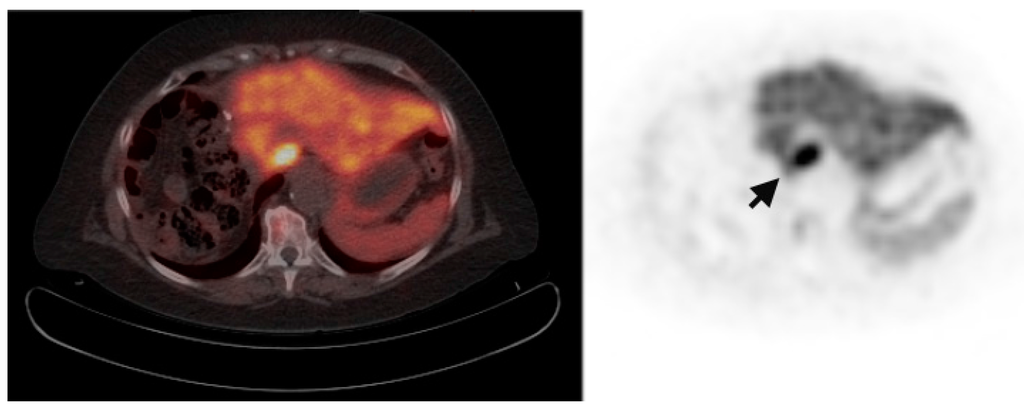

Multiple foci of increased FCh uptake in the liver consistent with multifocal or multinodular HCC (example, Figure 1) were noted in 8 of the 13 patients with increased primary tumor uptake. Of these, the areas of increased FCh uptake were adjacent to the treatment site (examples, Figure 2 and Figure 3) in 2 patients treated by local tumor ablation and 1 patient treated by liver resection. In one newly diagnosed case, PET demonstrated heterogeneous tumor FCh uptake with increased peripheral uptake and markedly diminished central uptake (Figure 4). Pathology in this case revealed a highly-necrotic tumor with Edmondson-Steiner grade 3 differentiation.

Figure 3.

Tumor recurrence near a resection margin. Corresponding PET/CT (left) and PET (right) images of the remnant liver status post partial right hepatectomy shows focal increased FCh uptake (arrow) adjacent to the resection margin. Histology confirmed this lesion as recurrent HCC.